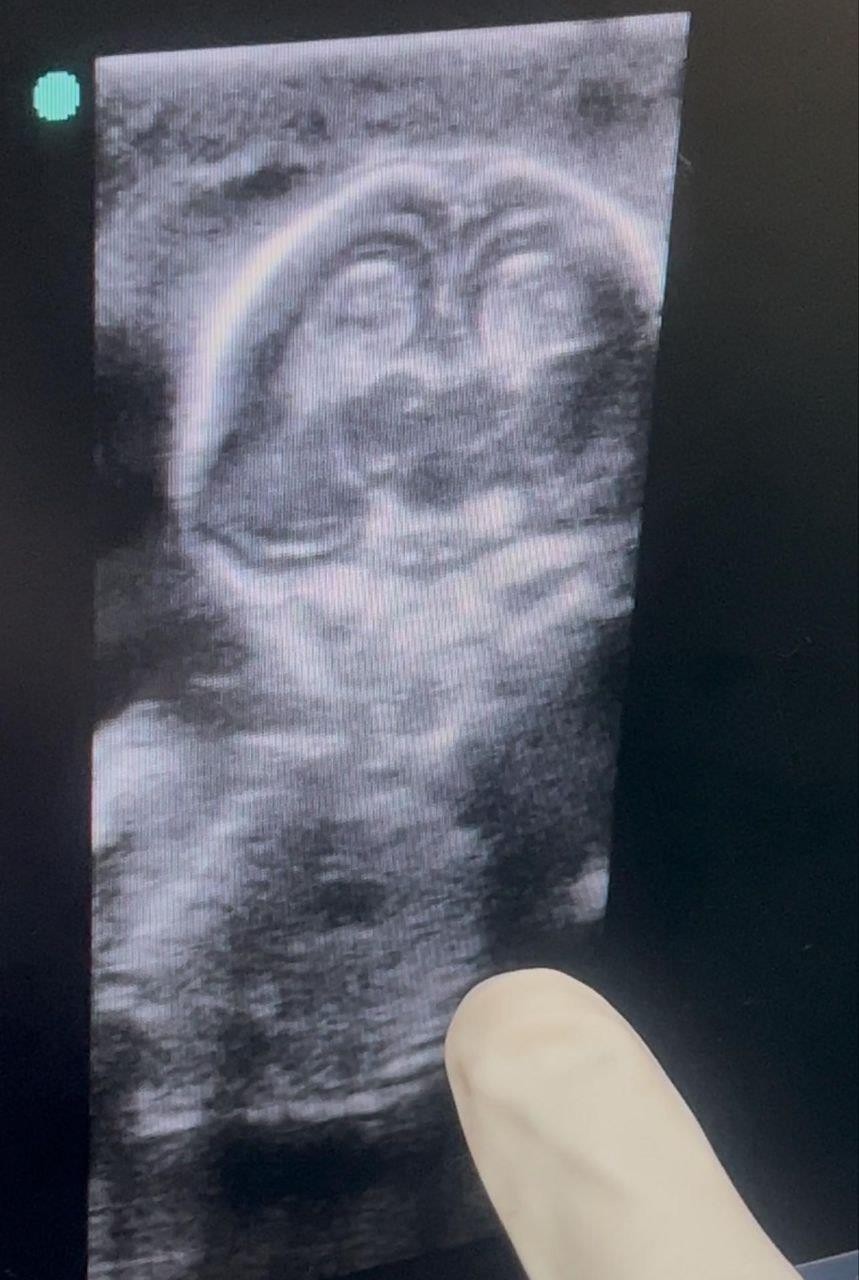

- Ultrasound (13–14 weeks): Live fetus, CRL 80.9 mm, FHR 168 bpm, no anomalies. Bilateral ovarian cysts noted (right ~69×51 mm, left ~32×24 mm) with papillary projections.

- MRI pelvis (12/07/2025): Right adnexal mass 75×55×46 mm, left adnexal mass 30× 25×53 mm, both complex with septations and vascular papillary projections; no extra-ovarian spread.